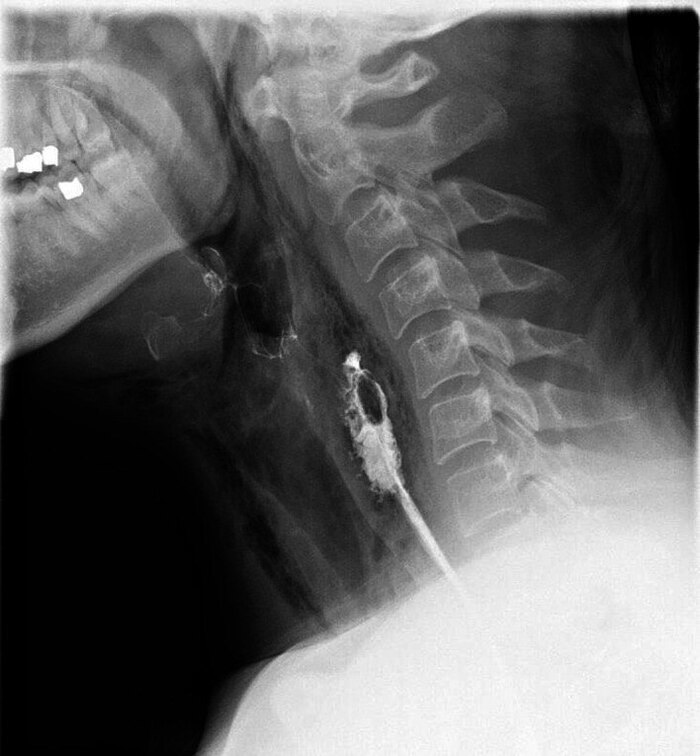

Рентгенограмма грудной клетки показала двустороннее проникновение воздуха в мягкие ткани шеи, латеральнее гортани и трахеи Фото 1, пневмоторакса не было.

Figure 1. Рентгенограмма грудной клетки показывает наличие внепросветного воздуха в мягких тканях шеи.